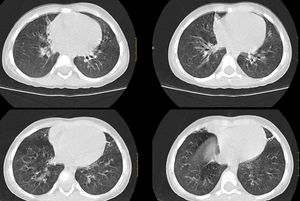

Ante la sospecha de síndrome aspirativo crónico por disfagia y posible reflujo gastroesofágico asociado (descartado posteriormente con pHmetría), se realizó tomografía computarizada pulmonar en la que se apreciaron atelectasias subsegmentarias en el lóbulo medio y la língula con pequeñas bronquiectasias y discreto engrosamiento intersticial peribroncovascular de predominio en lóbulos inferiores (fig. 1). Ante dichos hallazgos se realizó broncoscopia flexible en la que se observó abundante mucosidad en todo el árbol bronquial, con lavado broncoalveolar positivo a Haemophilus influenzae. Como tratamiento recibió budesonida inhalada y nasal, suero salino hipertónico nebulizado, fisioterapia respiratoria y azitromicina oral 3 días por semana.